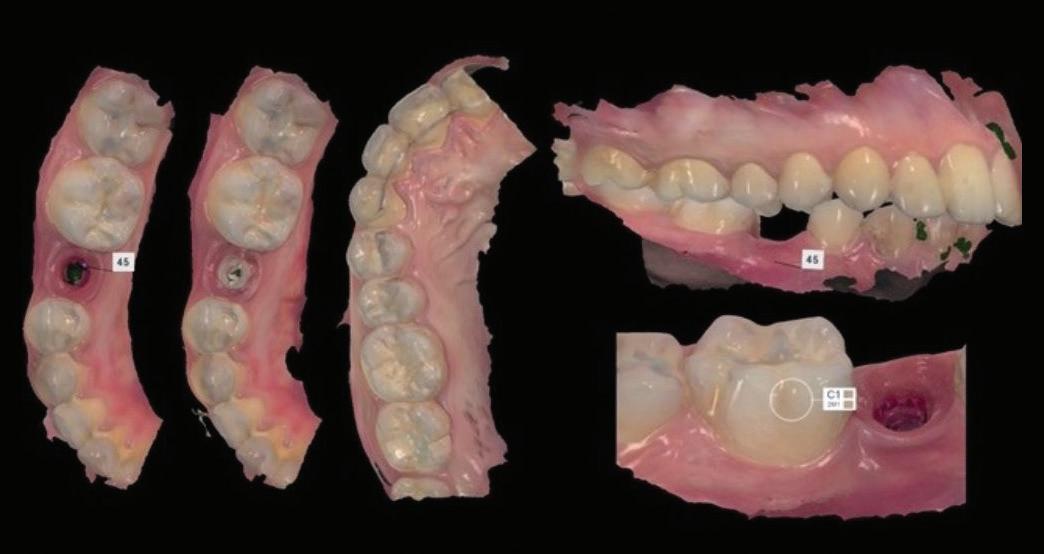

Figure 1: Radiographic Image of implants do not demonstrate bone loss due to the bisecting angle of the radiograph taken.

Figure 2: Radiographic image in a paralleling technique of implants dem onstrate moderate peri-implantitis with bone loss that will necessitate treatment.